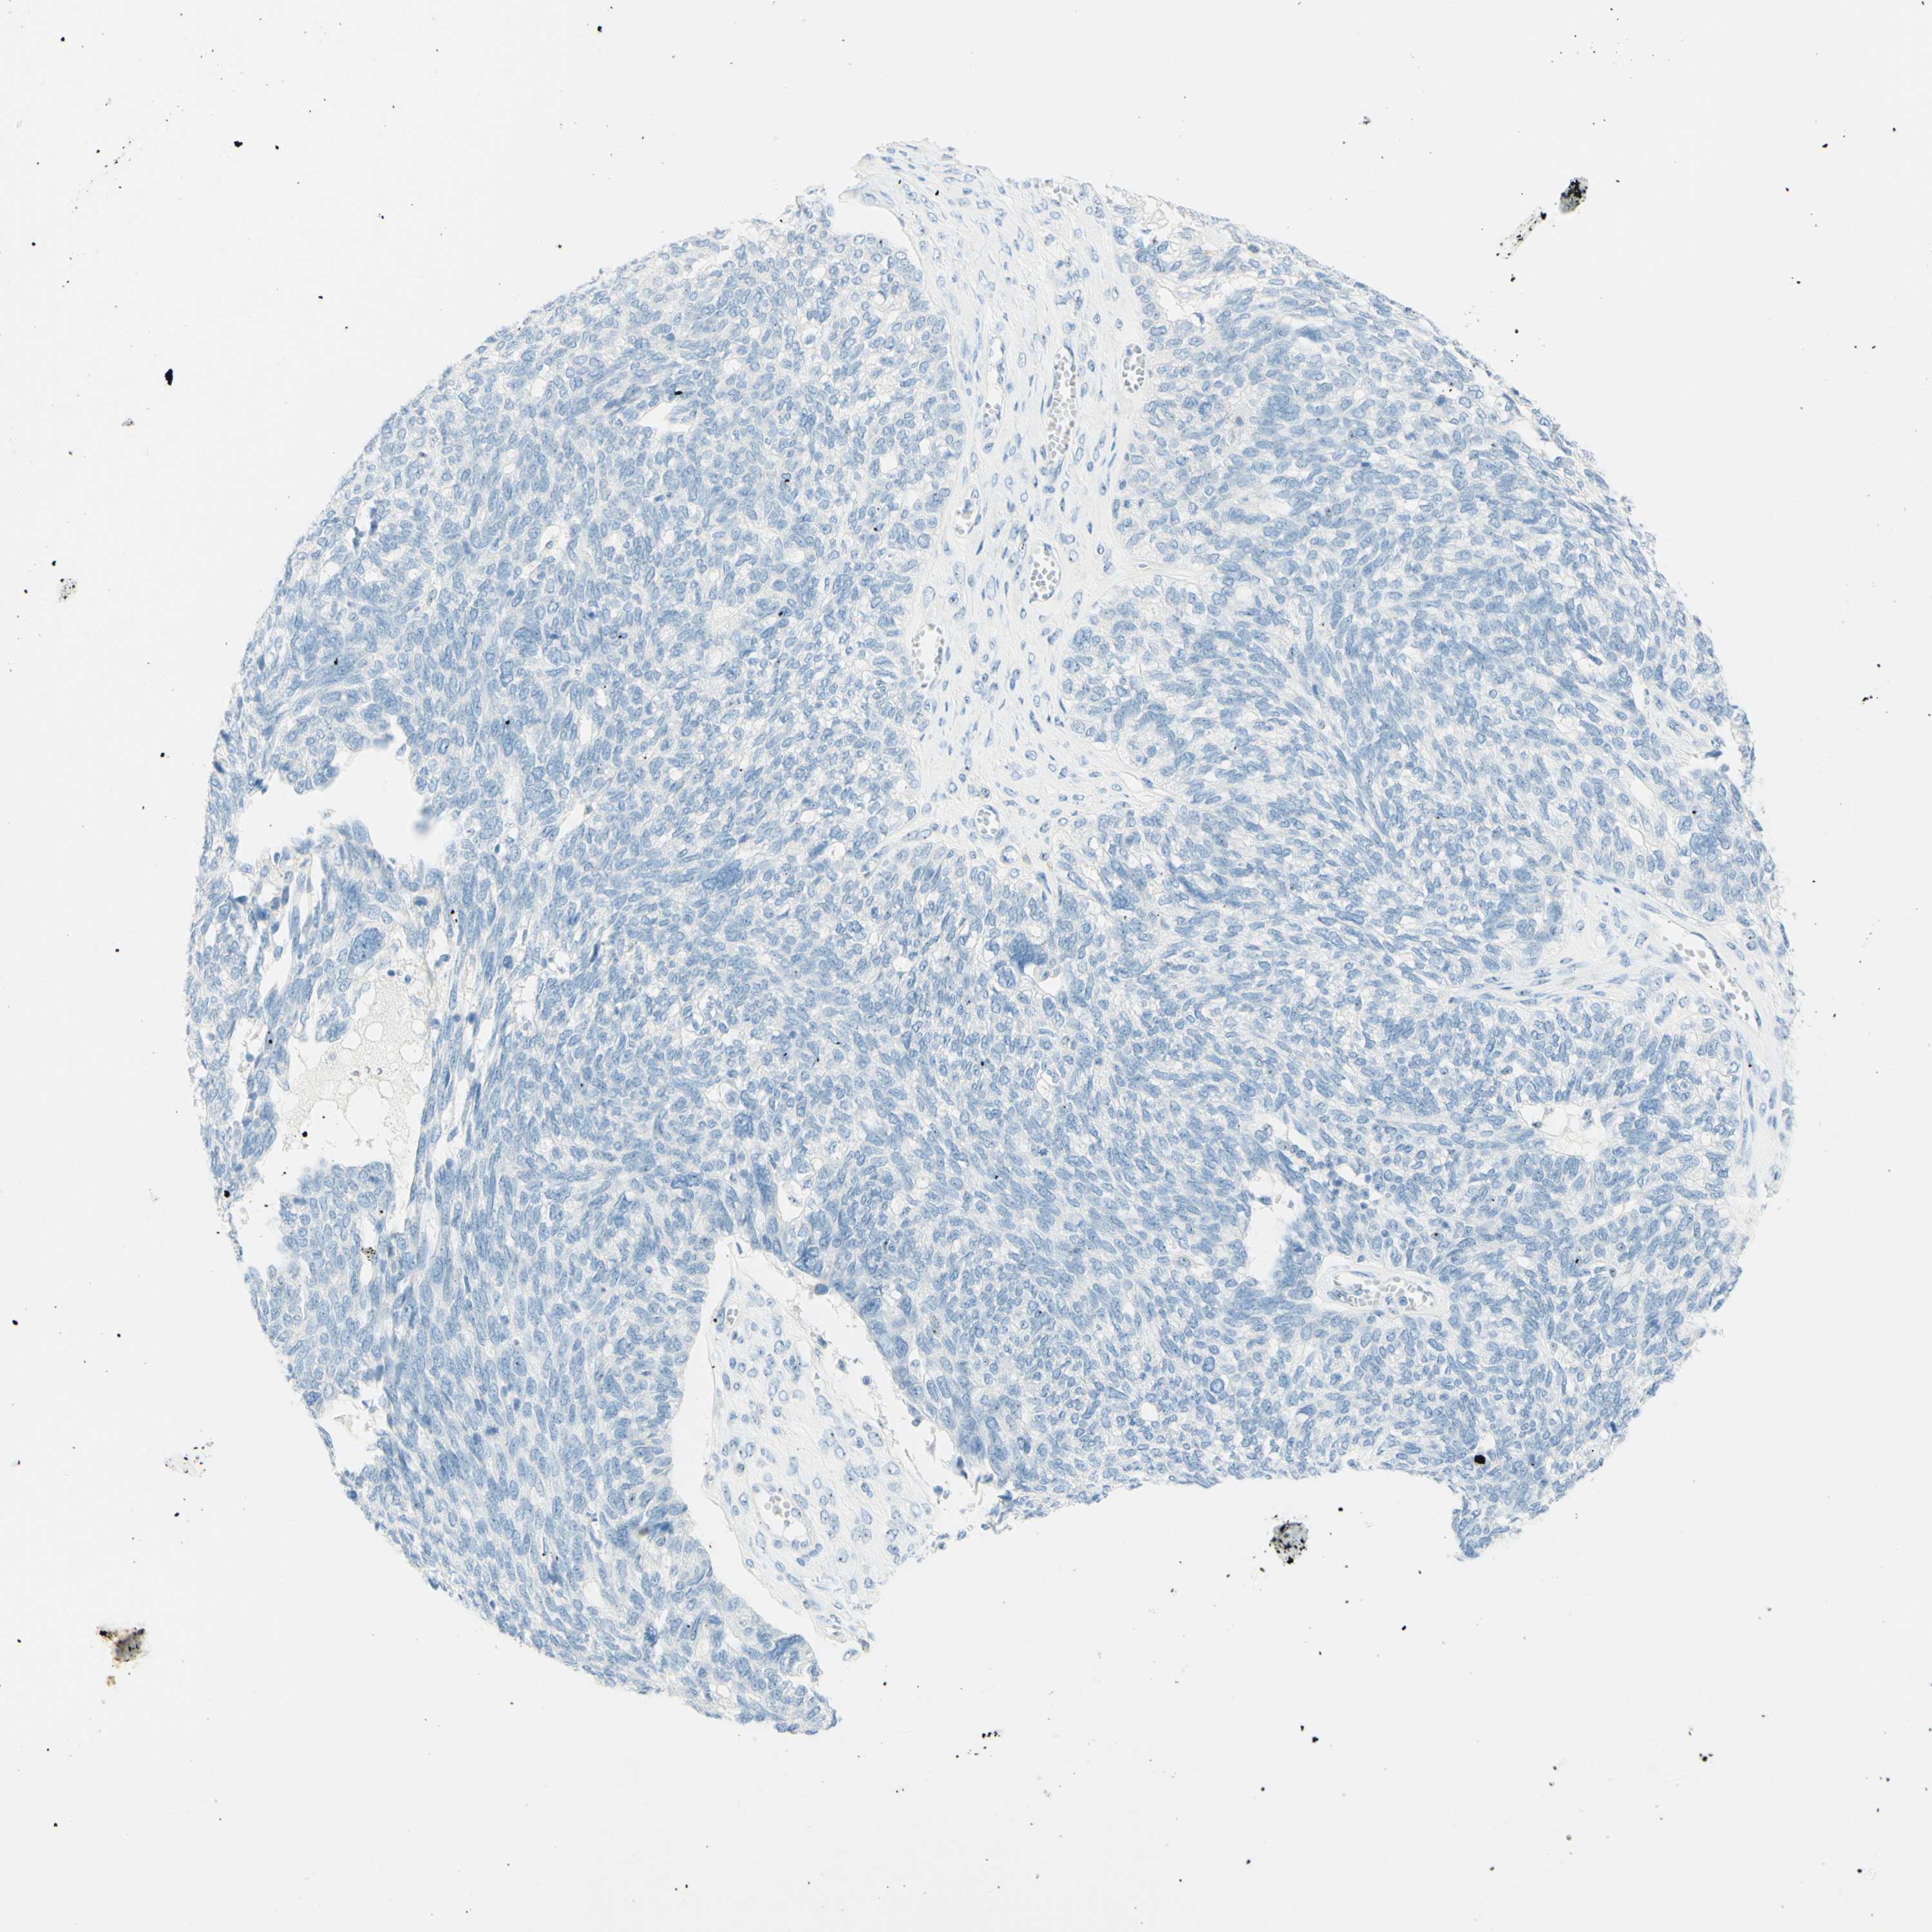

OVARIAN CANCER - Protein expressioni

A mouse-over function shows sample information and annotation data. Click on an image to view it in a full screen mode. Samples can be filtered based on level of antibody staining by selecting one or several of the following categories: high, medium, low and not detected. The assay and annotation is described here.

Note that samples used for immunohistochemistry by the Human Protein Atlas do not correspond to samples in the TCGA dataset.

Antibody stainingi

Antibody staining in the annotated cell types in the current human tissue is reported as not detected, low, medium, or high, based on conventional immunohistochemistry profiling in selected tissues. This score is based on the combination of the staining intensity and fraction of stained cells.

Each image is clickable and will lead to virtual microscopy that enables deeper exploration of all samples and also displays staining intensity scores, fraction scores and subcellular localization as well as patient and tissue information for each sample.

Antibody HPA011284

Antibody CAB026403

Cystadenocarcinoma, serous, NOS

Carcinoma, endometroid

Cystadenocarcinoma, mucinous, NOS

Carcinoma, NOS